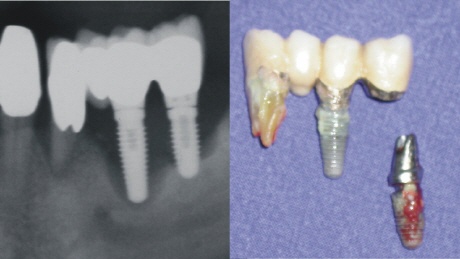

2. Mechanische Überbelastung des Implantats durch eine statisch ungünstige Versorgung.

Bei statischen Fehlkonstruktionen auf Implantaten ist quasi schon mit dem Einsetzen der Versorgung deren langfristiger Misserfolg besiegelt. Diese Misserfolge sind leider gehäuft, wenn das Einsetzen der Implantate und die Versorgung nicht in einer Hand (Praxis) bleiben.

Bei den heute nicht mehr üblichen Blattimplantaten, wie auch bei den nicht zu empfehlenden Diskimplantaten, waren/sind Brucherscheinungen keine Seltenheit. Der große Nachteil hierbei ist, dass die zwangläufige Entfernung des gebrochenen Implantats oftmals einen erheblichen Knochendefekt hinterlässt.